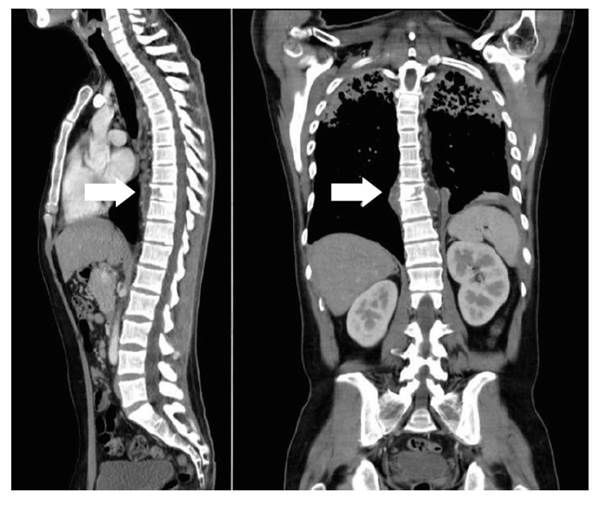

Durante la estancia en el hospital se realizaron análisis complementarios, siendo los resultados: leucocitos de 11 060 /µl, hemoglobina de 11 gr/dl, eosinófilos 1,9%, linfocitos 6,9%, proteína C reactiva 7,72 mg/dl, velocidad de sedimentación globular 67 mm/hora, deshidrogenasa láctica 279 U/l, fosfatasa alcalina 133 U/l y una prueba ELISA para VIH de cuarta generación no reactivo. De esta manera, dentro de los diagnósticos diferenciales se planteó un probable proceso neoformativo secundario a distancia, solicitándose una tomografía que incluyó los segmentos corporales de cabeza, tórax, abdomen y pelvis. Este estudio reportó “a nivel cerebral un quiste aracnoideo de 49 x 35 mm en el área temporal anterior izquierdo, una lesión pleuroparenquimal pulmonar de aspecto secuelar con escasa efusión pleural izquierda, adenopatías mediastinales reactivas, un área hipodensa de 34 x 29 mm en la región anterior periférica y una lesión osteolítica en cuerpo vertebral de D9” (figura 2). Asimismo, se amplió los estudios del dedo comprometido con una ecografía Doppler de la mano derecha que reportó una “lesión expansiva vascularizada en falange proximal del segundo dedo con compromiso óseo”. La resonancia magnética nuclear de dicho dedo evidenció una “lesión expansiva de 57 x 22 x 17,3 mm con fractura patológica en tercio medio diafisario de falange proximal de segundo dedo, con rebordes lobulados y efecto de masa desplazando el tendón flexor hacia palmar. Se observó también compromiso de articulación interfalángica proximal, y de la base de falange media. Tras la administración de contraste muestra ávido realce” (figura 3). Durante la hospitalización, los controles de BK de esputo, posterior a un mes de tratamiento con el esquema sensible, fue paucibacilar (8 BARR/100 campos).

Figura 2 Tomografía computarizada de tórax-abdomen-pelvis con contraste: lesión pleuroparenquimal con efusión pleural izquierda. Lesión osteolítica en cuerpo vertebral de D9 (flecha blanca)